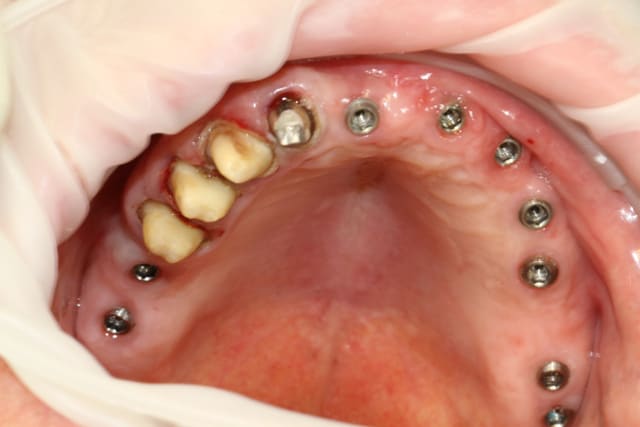

Sinon, tu préfères peut-etre ça

je trouve le pts de contact 26/27 pas trop large , faut faire gaffe aux débris fibreux qui viennent s'y coincer ! ;)